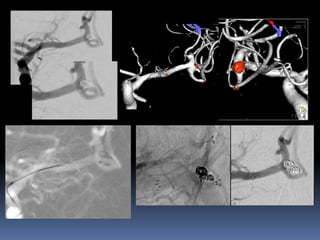

Circumferential involvement-End hole

Broad neck , dyplastic aneurysms

A

B

C

large-/giant aneurysms